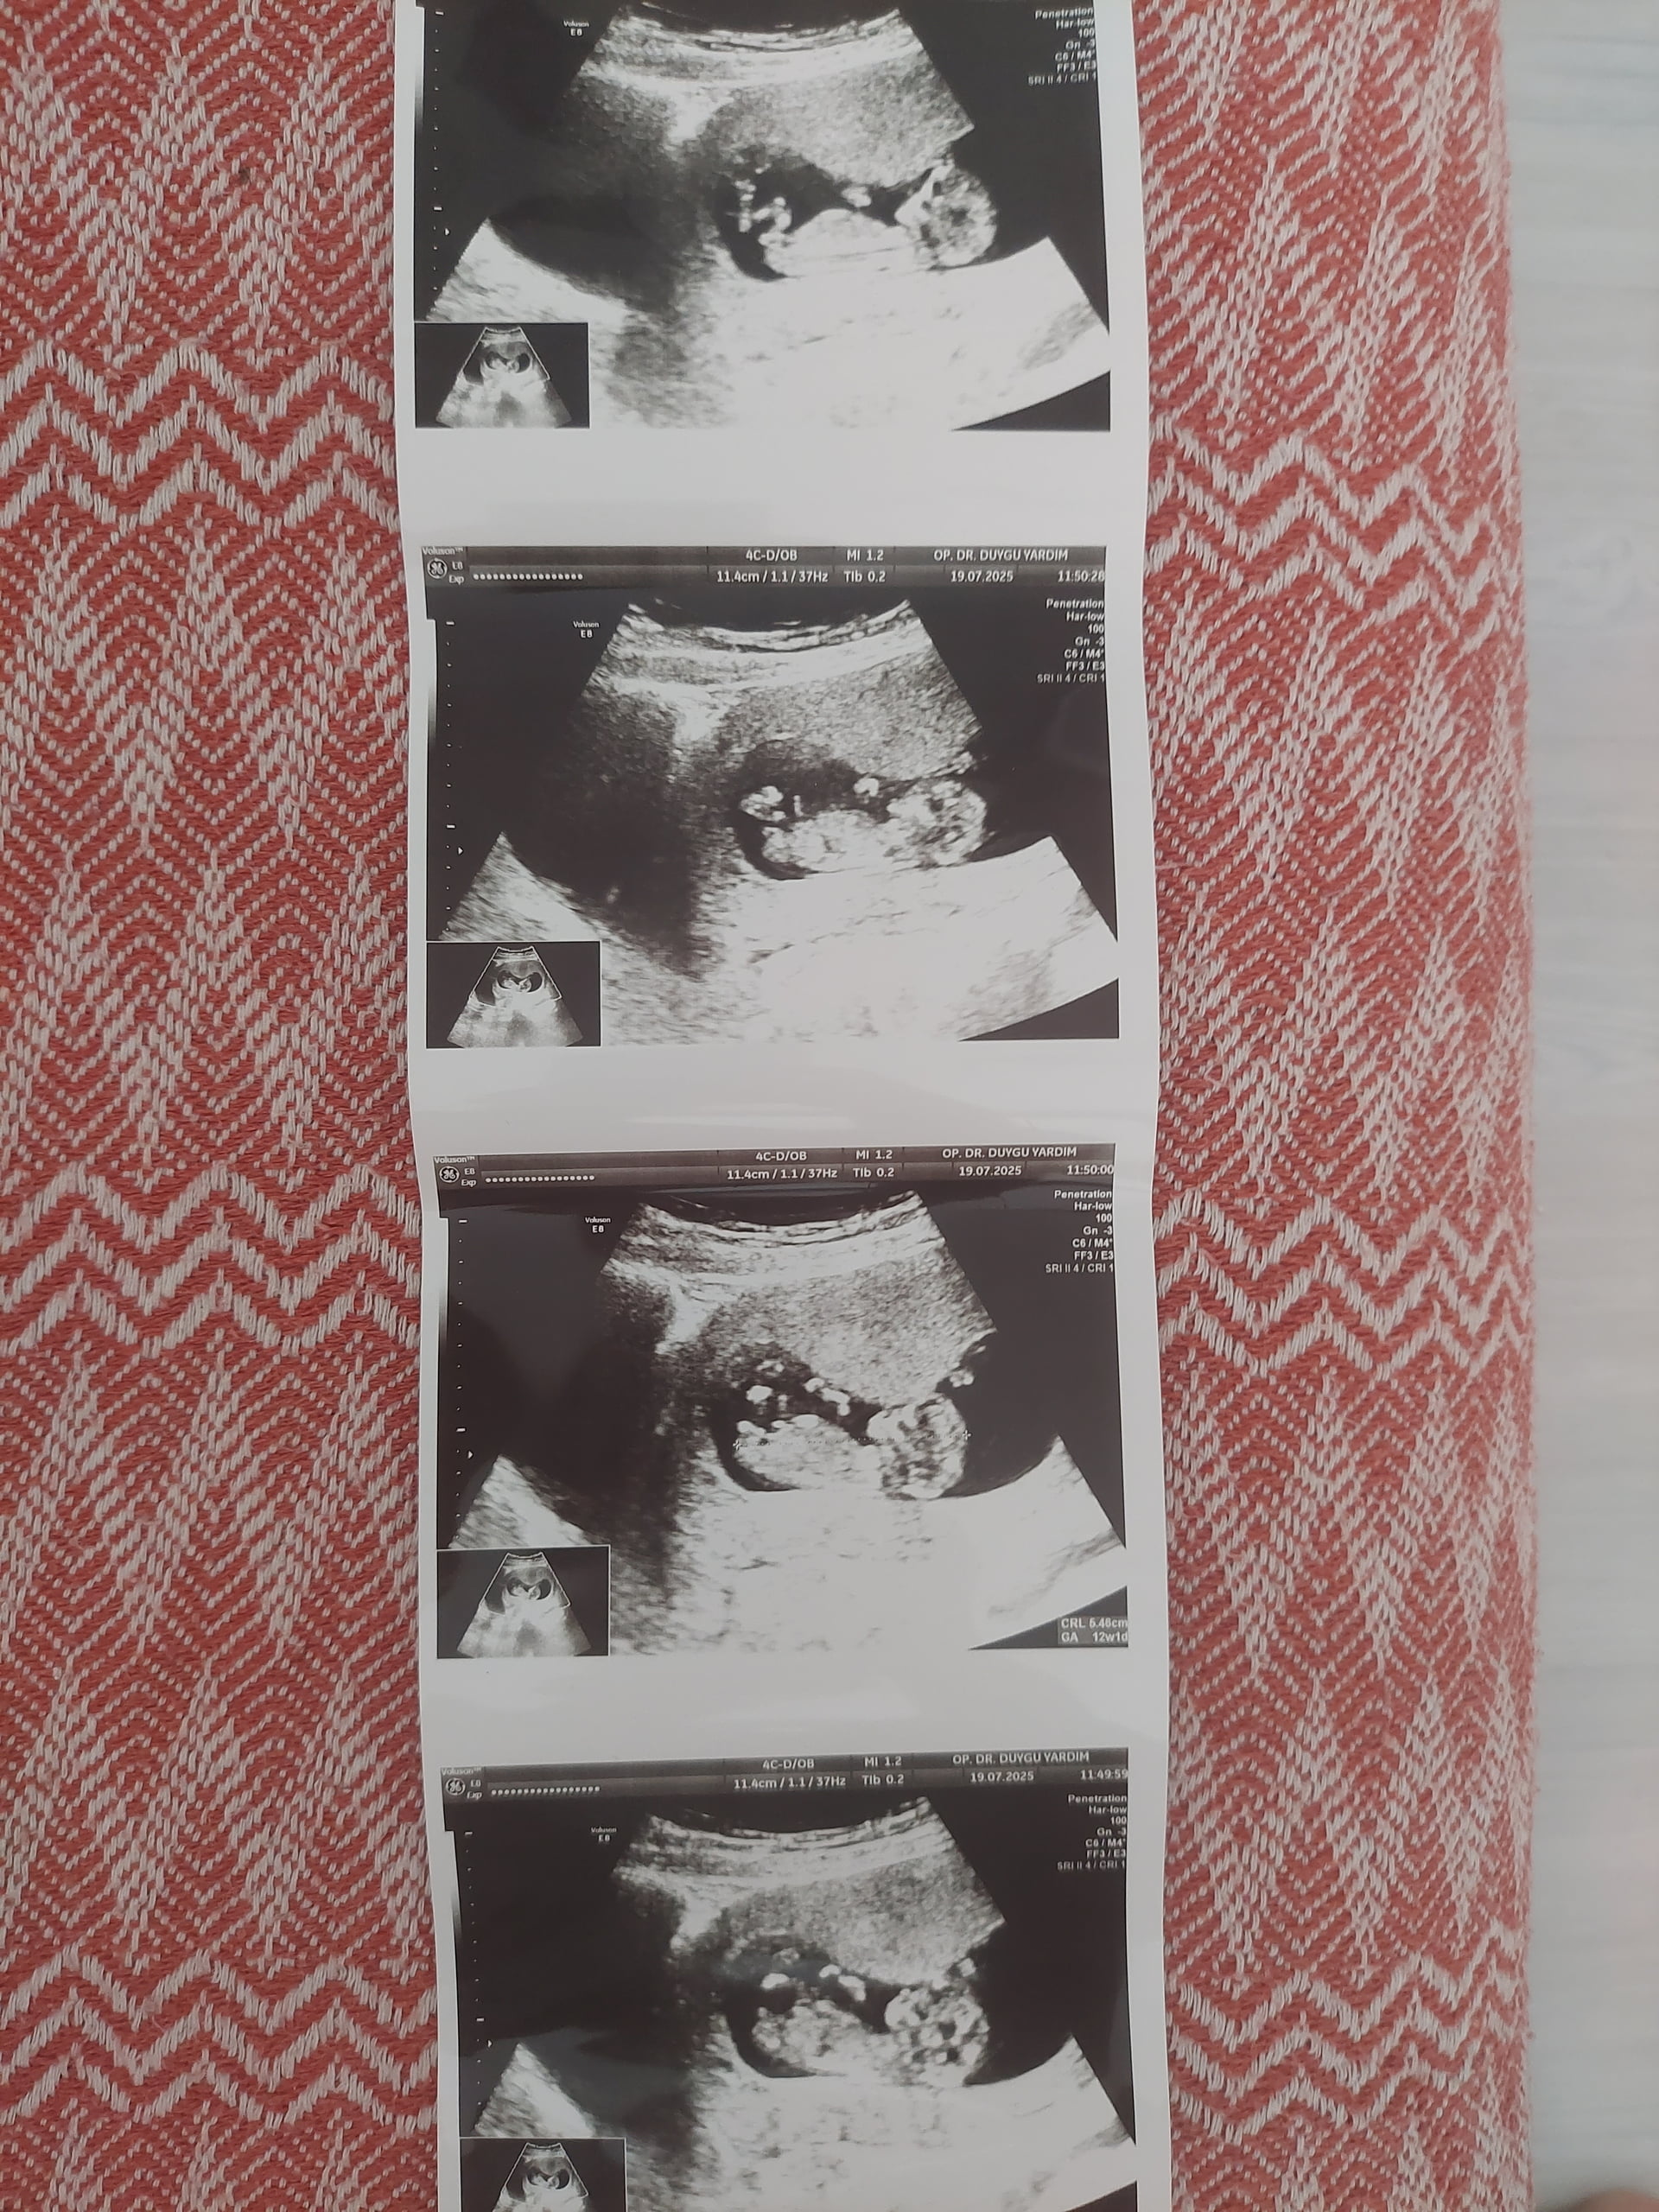

Erkek gibi kuzum

Evet canım bildin Erkek ![]()

Erkek bebiş kuzum ![]()